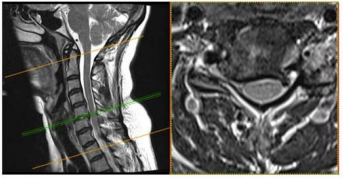

Uma paciente de 47 anos de idade apresenta quadro de cervicobraquialgia direita há cerca de três meses, associada a parestesia no membro superior direito, que se estende até mão, principalmente nos dedos indicador e polegar. Ao exame fisico, nota-se leve redução do reflexo braquioestilorradial. O teste de Spurling foi positivo à direita. Observou-se ausência de paresias.

Enunciado 4721135-1

No citado caso clínico, foi solicitada uma ressonância magnética cervical, conforme representado nas figuras. Esse exame evidencia uma